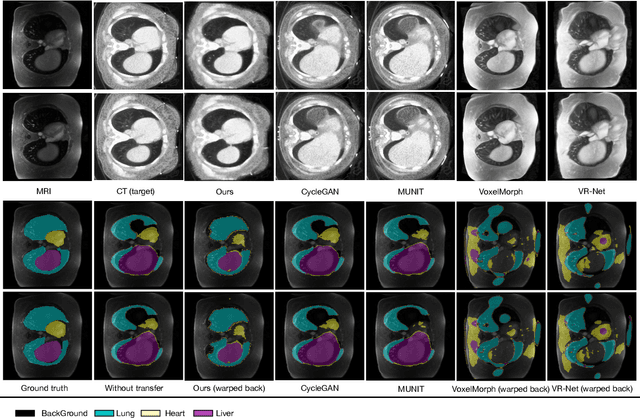

Abstract:Generative models have been widely proposed in image recognition to generate more images where the distribution is similar to that of the real images. It often introduces a discriminator network to discriminate original real data and generated data. However, such discriminator often considers the distribution of the data and did not pay enough attention to the intrinsic gap due to structure. In this paper, we reformulate a new image to image translation problem to reduce structural gap, in addition to the typical intensity distribution gap. We further propose a simple yet important Structure Unbiased Adversarial Model for Medical Image Segmentation (SUAM) with learnable inverse structural deformation for medical image segmentation. It consists of a structure extractor, an attention diffeomorphic registration and a structure \& intensity distribution rendering module. The structure extractor aims to extract the dominant structure of the input image. The attention diffeomorphic registration is proposed to reduce the structure gap with an inverse deformation field to warp the prediction masks back to their original form. The structure rendering module is to render the deformed structure to an image with targeted intensity distribution. We apply the proposed SUAM on both optical coherence tomography (OCT), magnetic resonance imaging (MRI) and computerized tomography (CT) data. Experimental results show that the proposed method has the capability to transfer both intensity and structure distributions.